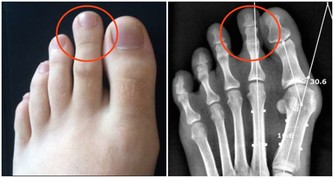

關節響可能是疾病徵兆

如果開始出現這樣的情況,一定要警惕,就可能是疾病的徵兆。

當人的年齡增大後,關節潤滑液會越來越少,潤滑度不夠,關節必定會出現磨損,這時候就會出現關節炎、骨刺、骨質疏鬆等疾病。

嚴重的甚至會導致骨關節壞死,這種屬於病理性關節響,一般伴隨著疼痛、活動受限,或者關節突然卡住。